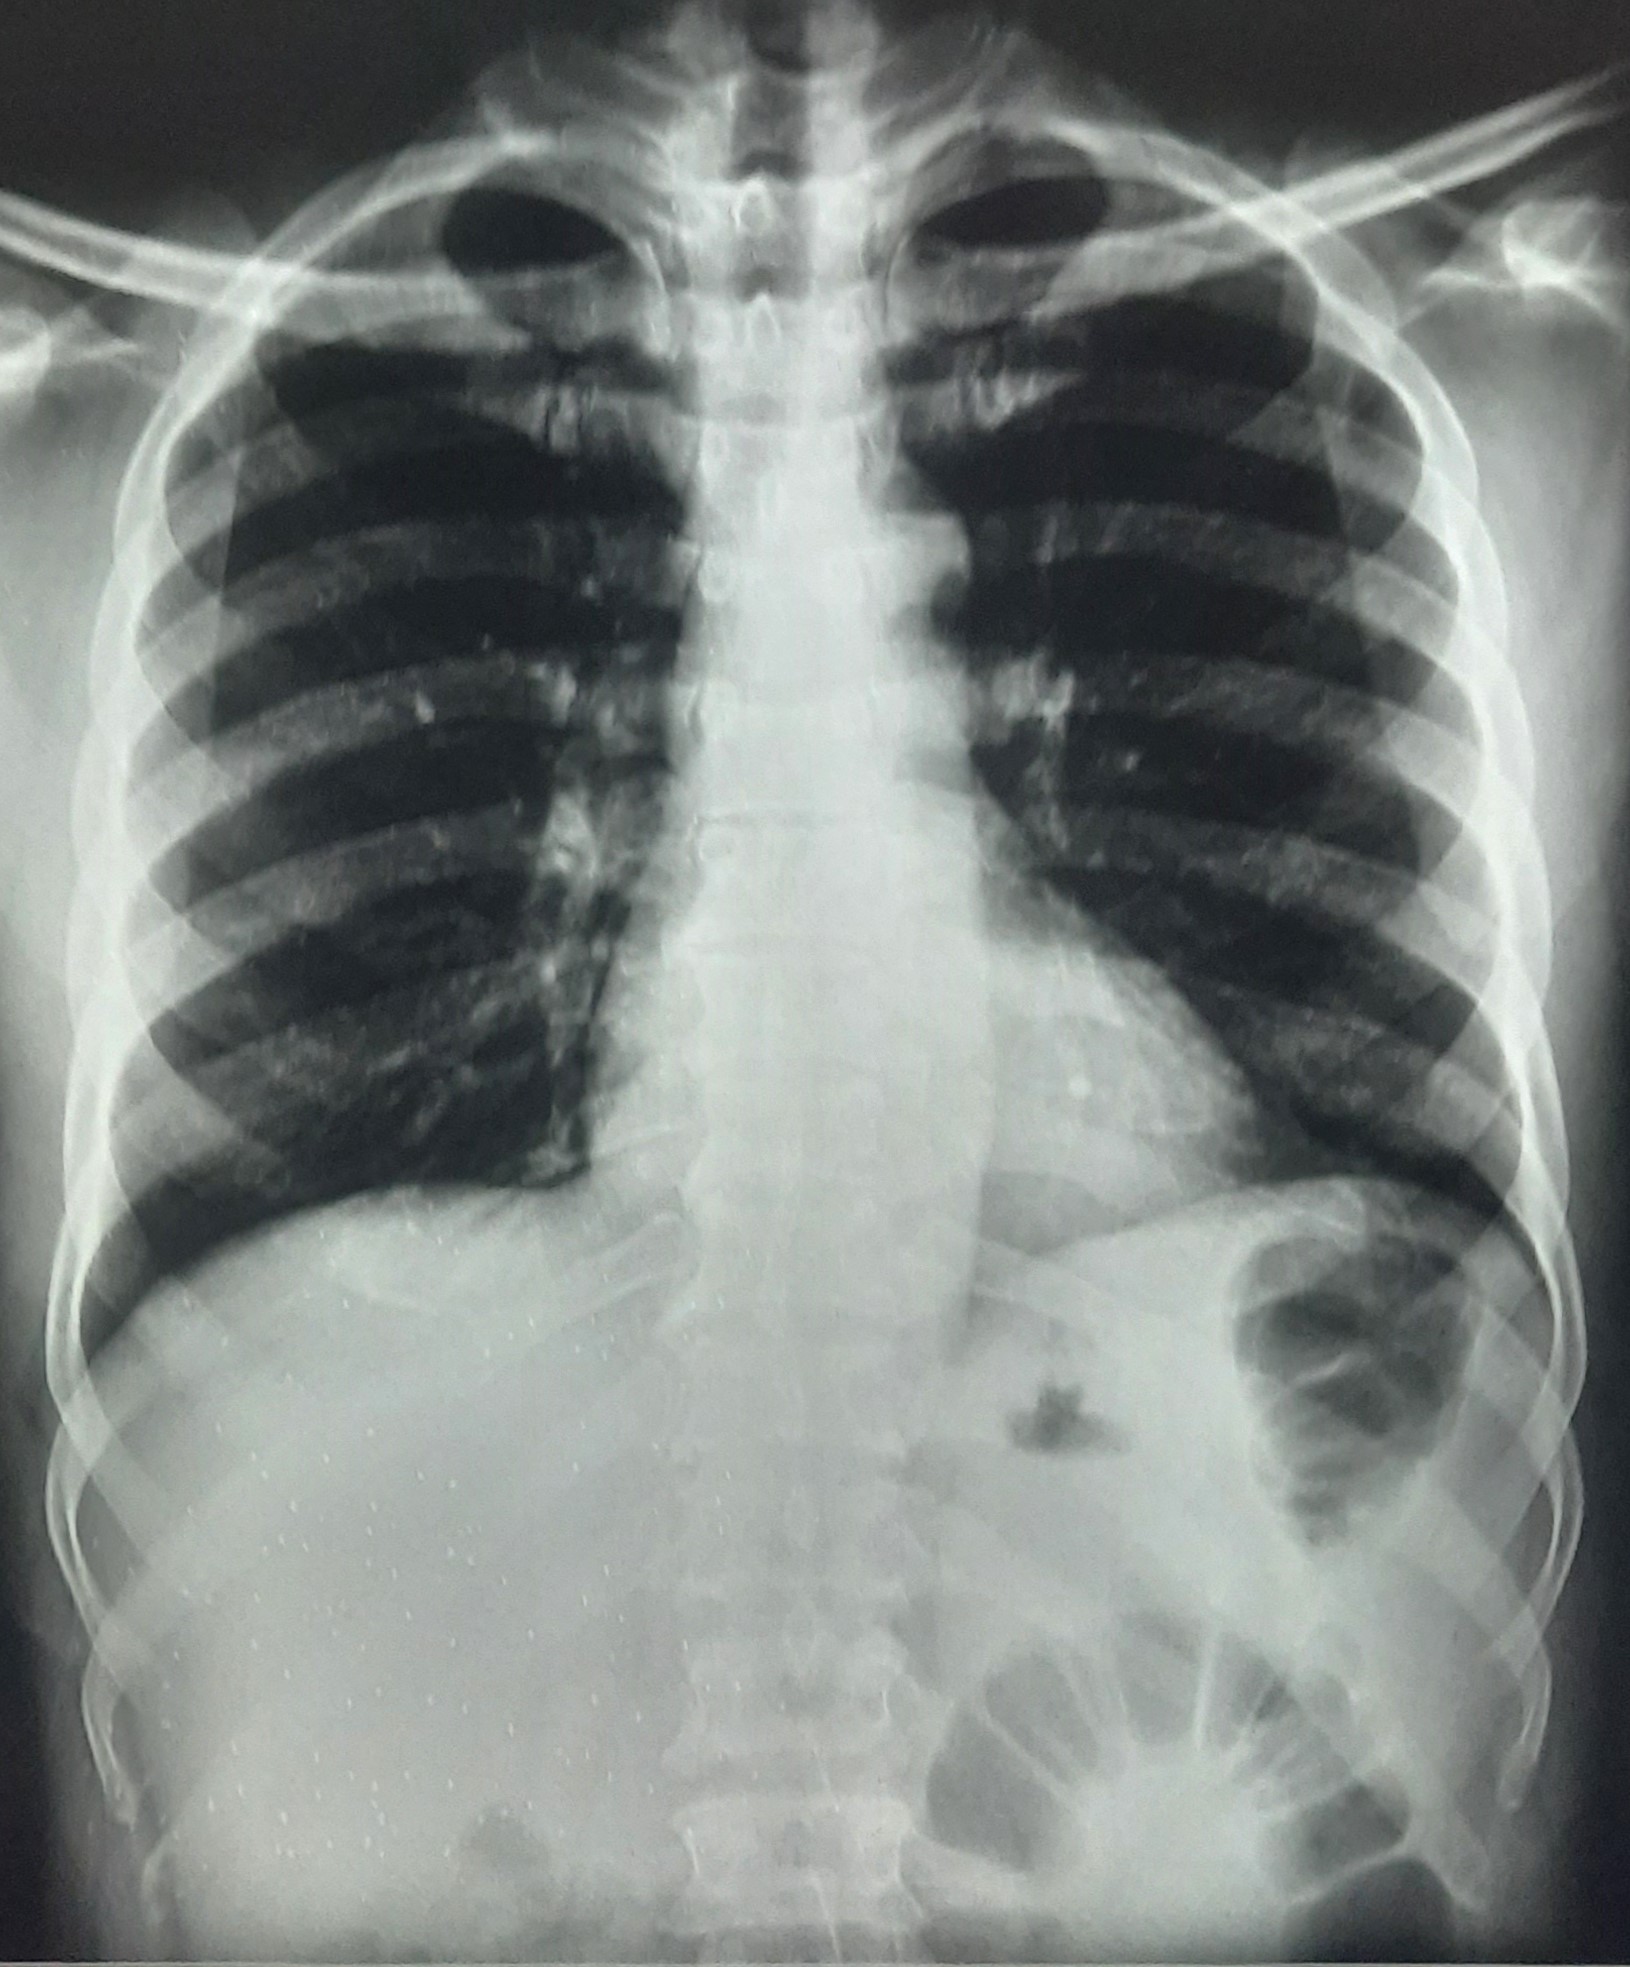

| 295 | IGGMC, Nagpur, Nagpur | P2 | 29-4177 | Afra Firdos | Consent taken on Paper | 14 Yrs. |

Provisional Diag : Pleural Effusion ?

Final Diag : Pleural Effusion |

Result awaited (Suspected TB/Non-TB) | Right Sided Pleural Effusion | Abnormality visible on x-ray |